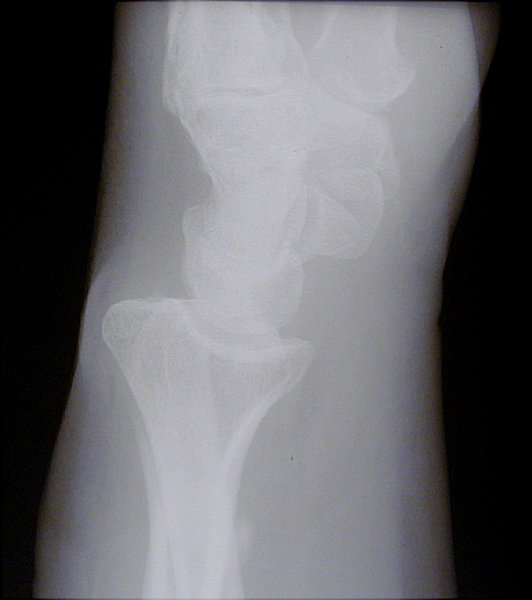

Return to Barton Fracture